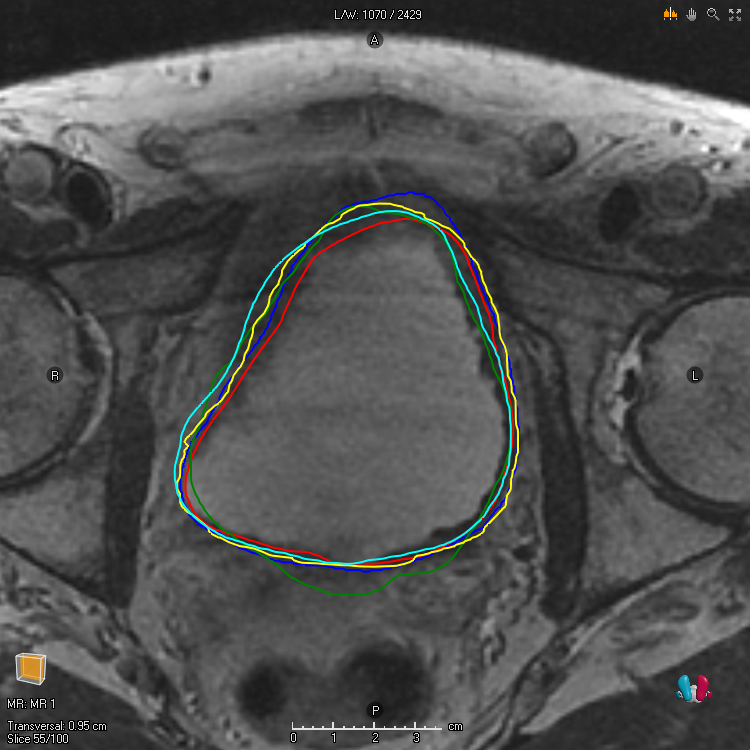

We study two of the most popular performance metrics in medical image segmentation, Accuracy and Dice, when the target labels are noisy. For both metrics, several statements related to characterization and volume properties of the set of optimal segmentations are proved, and associated experiments are provided. Our main insights are: (i) the volume of the solutions to both metrics may deviate significantly from the expected volume of the target, (ii) the volume of a solution to Accuracy is always less than or equal to the volume of a solution to Dice and (iii) the optimal solutions to both of these metrics coincide when the set of feasible segmentations is constrained to the set of segmentations with the volume equal to the expected volume of the target.